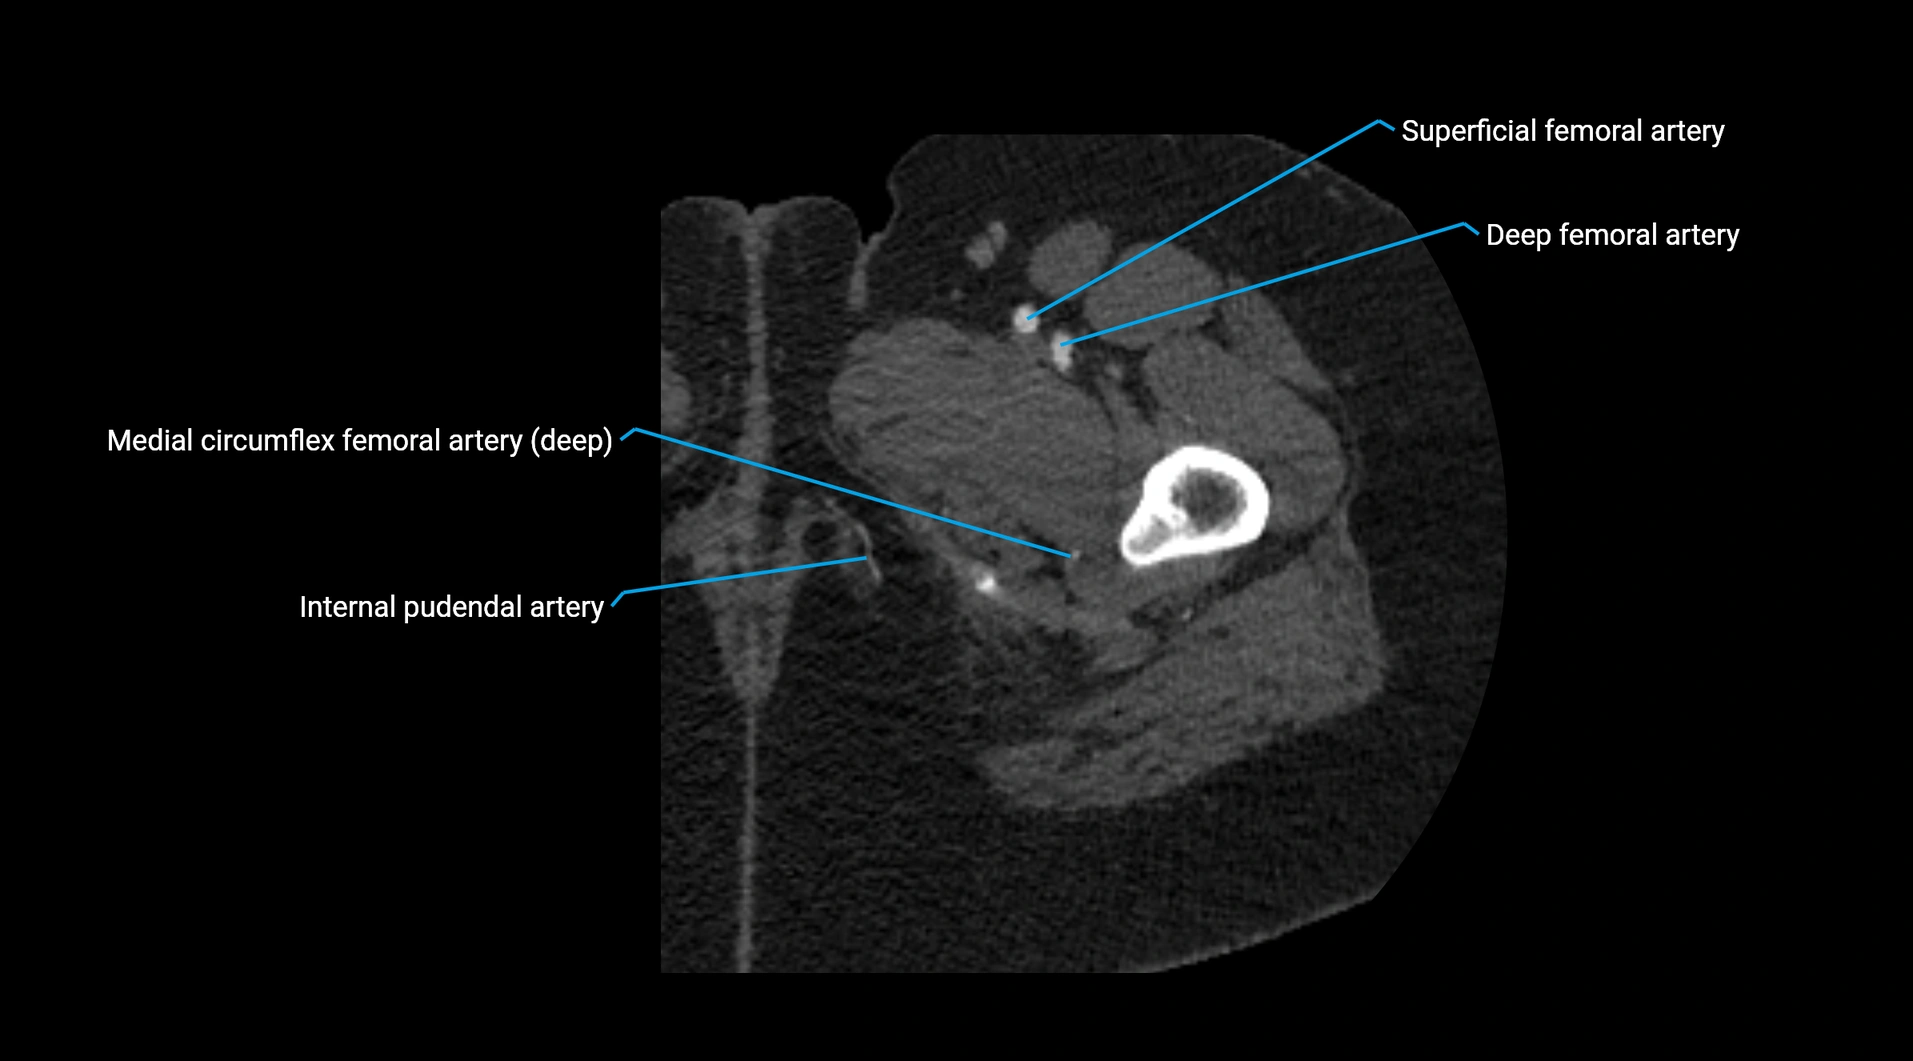

CT images

image